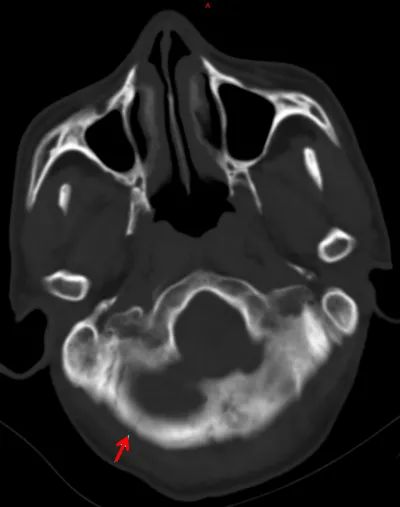

每年自然環(huán)境對(duì)個(gè)人的輻射量約是3mSv(毫希伏),而1次腹部、脊柱或全身CT的輻射量約為10mSv,是自然環(huán)境下3年的輻射總量;1次胸部CT相當(dāng)于1個(gè)人2年多接受的輻射量,頭部、心臟CT的輻射劑量小一些,一次也有2mSv。多次重復(fù)CT檢查,輻射劑量和相應(yīng)危害可以累加,癌癥的發(fā)生率就可能增加。